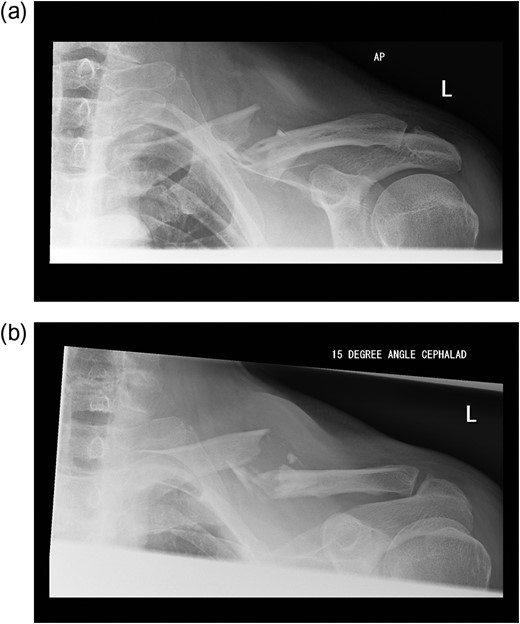

A 60-year-old gentleman presented with a displaced multifragmentary fracture of the left clavicle after a fall from a ladder. After discussion regarding the risks and benefits regarding operative versus non-operative treatment he elected for fixation (Fig. 1).

(a and b) Pre-operative radiographs of the fractured clavicle.